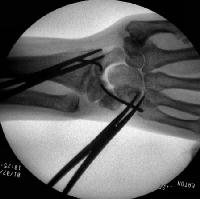

Intraoperative correction of scapholunate rotation using K-wires as joysticks on each bone.

Click for larger image

Scapholunate pins and bone anchors - intraoperative fluoroscopy.